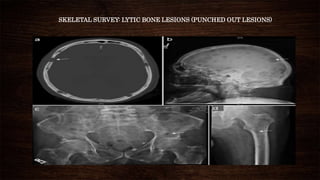

SKELETAL SURVEY: LYTIC BONE LESIONS (PUNCHED OUT LESIONS)

• SKELETAL SURVEY:A skeletal survey is comprised of various x-rays of all the bones in the body.

Typically, this procedure involves radiographs of the skull, spine, humeri, ribs, pelvis and femora.

 Osteopenia in early stages

 Lytic bone lesions in advanced disease

 Osteosclerotic lesions in POEMS syndrome.(exception)